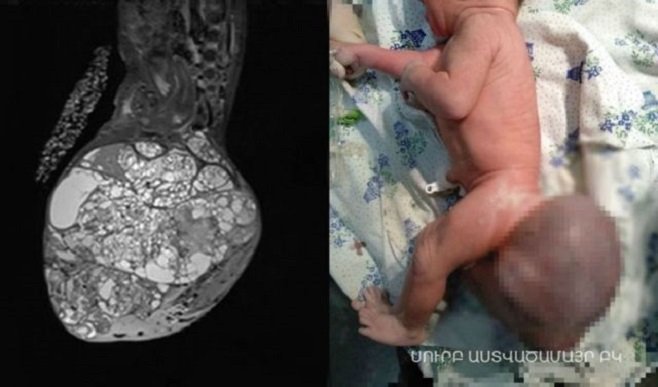

Հայ բժիշկները կատարել են հազվագյուտ վիրահատություն, որի շնորհիվ հաջողվել է փրկել նորածին երեխայի կյանքը։ Փոքրիկը ծնվել է 9 ամսականում 2,55 կգ քաշով, որից 1,2 կգ-ը եղել է բնածին ուռուցքը՝ տերատոման, որը տեղակայված էր կոնքային հատվածում։

ԲԿ-ի վերակենդանացման բաժնի վարիչ Չոբանյանի խոսքով՝ վիրահատությունը բացառիկ էր առաջին հերթին տերատոմայի չափերով․ «Տերատոմայի ծավալը շատ մեծ էր՝ երեխայի քաշի 1/3-ի չափով, կար ներանոթային մակարդման համախտանիշ, այսինքն՝ կային տրոմբիկներ այդ գոյացության մեջ, այն շատ արյունատար էր, երեխայի հեմոգլոբինն էր իջնում, կարիք ուներ արյան փոխներարկման։ Հետվիրահատական առաջին օրերին ընդհանուր ծանր վիճակ էր, բայց բարեհաջոց հաղթահարվեց։ Երեխան ոտքերը շարժում է, կոնքային խանգարումներ չունի, մնացած օրգանները նորմայի մեջ են»։

Երեխայի կոնքային հատվածի օրգանների ֆունկցիոնալ խանգարման ռիսկ է եղել, սակայն բժիշկներին հաջողվել է խուսափել դրանից։

«Ուռուցքը վավականին լուրջ փոխհարաբերություններ ուներ ներքին օրգանների, ուղիղ աղիքի, ողնաշարի հետ, եւ այստեղ ֆունկցիոն համակարգի խանգարումների ռիսկը մեծ էր, բայց մեղ հաջողվեց ամբողջովին վերացնել այն։ Ուռուցքը տենդենց ուներ աճելու, համարվում է չարօրիակ ուռուցք, բայց նորածնային շրջանում հեռացումը բերում է լիարժեք առողջացման։ Սովորաբար հղիության ժամանակ հայտնաբերման դեպքում կոնսուլիում է գումարվում՝ որոշելու նման արատի դեպքում շանս կա՞ առողջացման, թե ոչ, եւ այդ ժամանակ տրվում է համապատասխան խորհուրդ։ Տվյալ դեպքում 50/50 էր հավանականությունը առողջացման, եւ վիրահատությունը բարեհաջող կատարվեց», - ներկայացրեց ԲԿ-ի տնօրեն, վիրաբույժ Նիկոլայ Դալաքյանը։